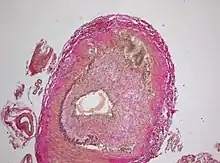

Biopsy

The gold standard for diagnosing temporal arteritis is biopsy, which involves removing a small part of the vessel under local anesthesia and examining it microscopically for giant cells infiltrating the tissue.[23] However, a negative result does not definitively rule out the diagnosis; since the blood vessels are involved in a patchy pattern, there may be unaffected areas on the vessel and the biopsy might have been taken from these parts. Unilateral biopsy of a 1.5–3 cm length is 85-90% sensitive (1 cm is the minimum).[24] Characterised as intimal hyperplasia and medial granulomatous inflammation with elastic lamina fragmentation with a CD 4+ predominant T cell infiltrate, currently biopsy is only considered confirmatory for the clinical diagnosis, or one of the diagnostic criteria.[11]